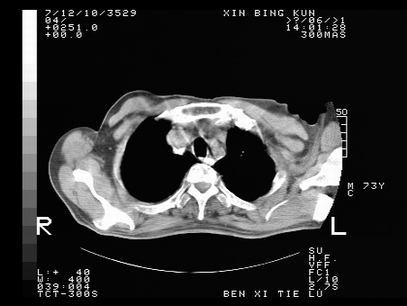

标题: CT10820:男,73岁,病史肺TB,现病史肺炎,直肠CA术后 [打印本页]

标题: CT10820:男,73岁,病史肺TB,现病史肺炎,直肠CA术后

1.两肺结核.2.两肺多发转移瘤.3右侧少量胸腔积液4.主动脉钙化.

1两肺结核2右侧胸腔积液3主动脉硬化

左肺上叶下叶背段,右肺中下叶见多发斑片状、条索状高密度影,兵变周围小结节影形成“树芽”样改变。 左肺上叶舌段近前胸壁处及右肺中叶内侧段见结节影。右侧胸膜腔内见液体密度区。纵隔内未见明确增大淋巴结。考虑左肺上叶舌段近前胸壁处及右肺中叶转移瘤可能性大。两肺继发型肺结核。右侧胸腔积液。

1.两肺结核.2.两肺多发转移瘤.3右侧少量胸腔积液4.主动脉钙化

支持:两肺结核.2.两肺多发转移瘤.3右侧少量胸腔积液4.主动脉钙化.

还有心包少量积液。